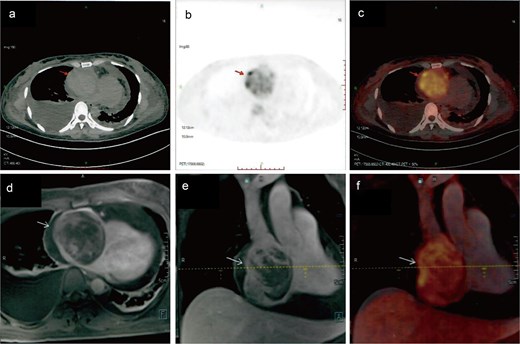

A 41-year-old female was admitted to our hospital with chest tightness and dyspnea for the past 2 weeks. Physical examination revealed bilateral lower limb edema without cardiac murmurs or jugular venous distention. Laboratory findings were notable for hypoalbuminemia (30 g/L) and an elevated D-dimer level (6.99 mg/mL), without remarkable blood routine examination and serum chemistry. Electrocardiography demonstrated sinus tachycardia and low-voltage complexes (Fig. 1). Echocardiography identified a large, well-demarcated hypoechoic mass (82 × 54 × 58 mm), nearly occupying the entire right atrial cavity (Fig. 2a and b). Contrast-enhanced computed tomography confirmed right pleural effusion and a right atrial occupying lesion (Fig. c and d). Subsequent right thoracentesis revealed exudative fluid with no evidence of malignancy on cytological examination. Further metabolic imaging with PET-CT (Fig. 3a and b) and PET-MR (Fig. 3c and d) demonstrated a hypermetabolic soft tissue mass within the right atrium, highly suggestive of primary cardiac angiosarcoma, with no signs of distant metastasis.

Metabolic imaging. PET-CT (a) and (b) and PET-MR (c) and (d) demonstrated a hypermetabolic soft tissue mass within the right atrium, highly suggestive of primary cardiac angiosarcoma.